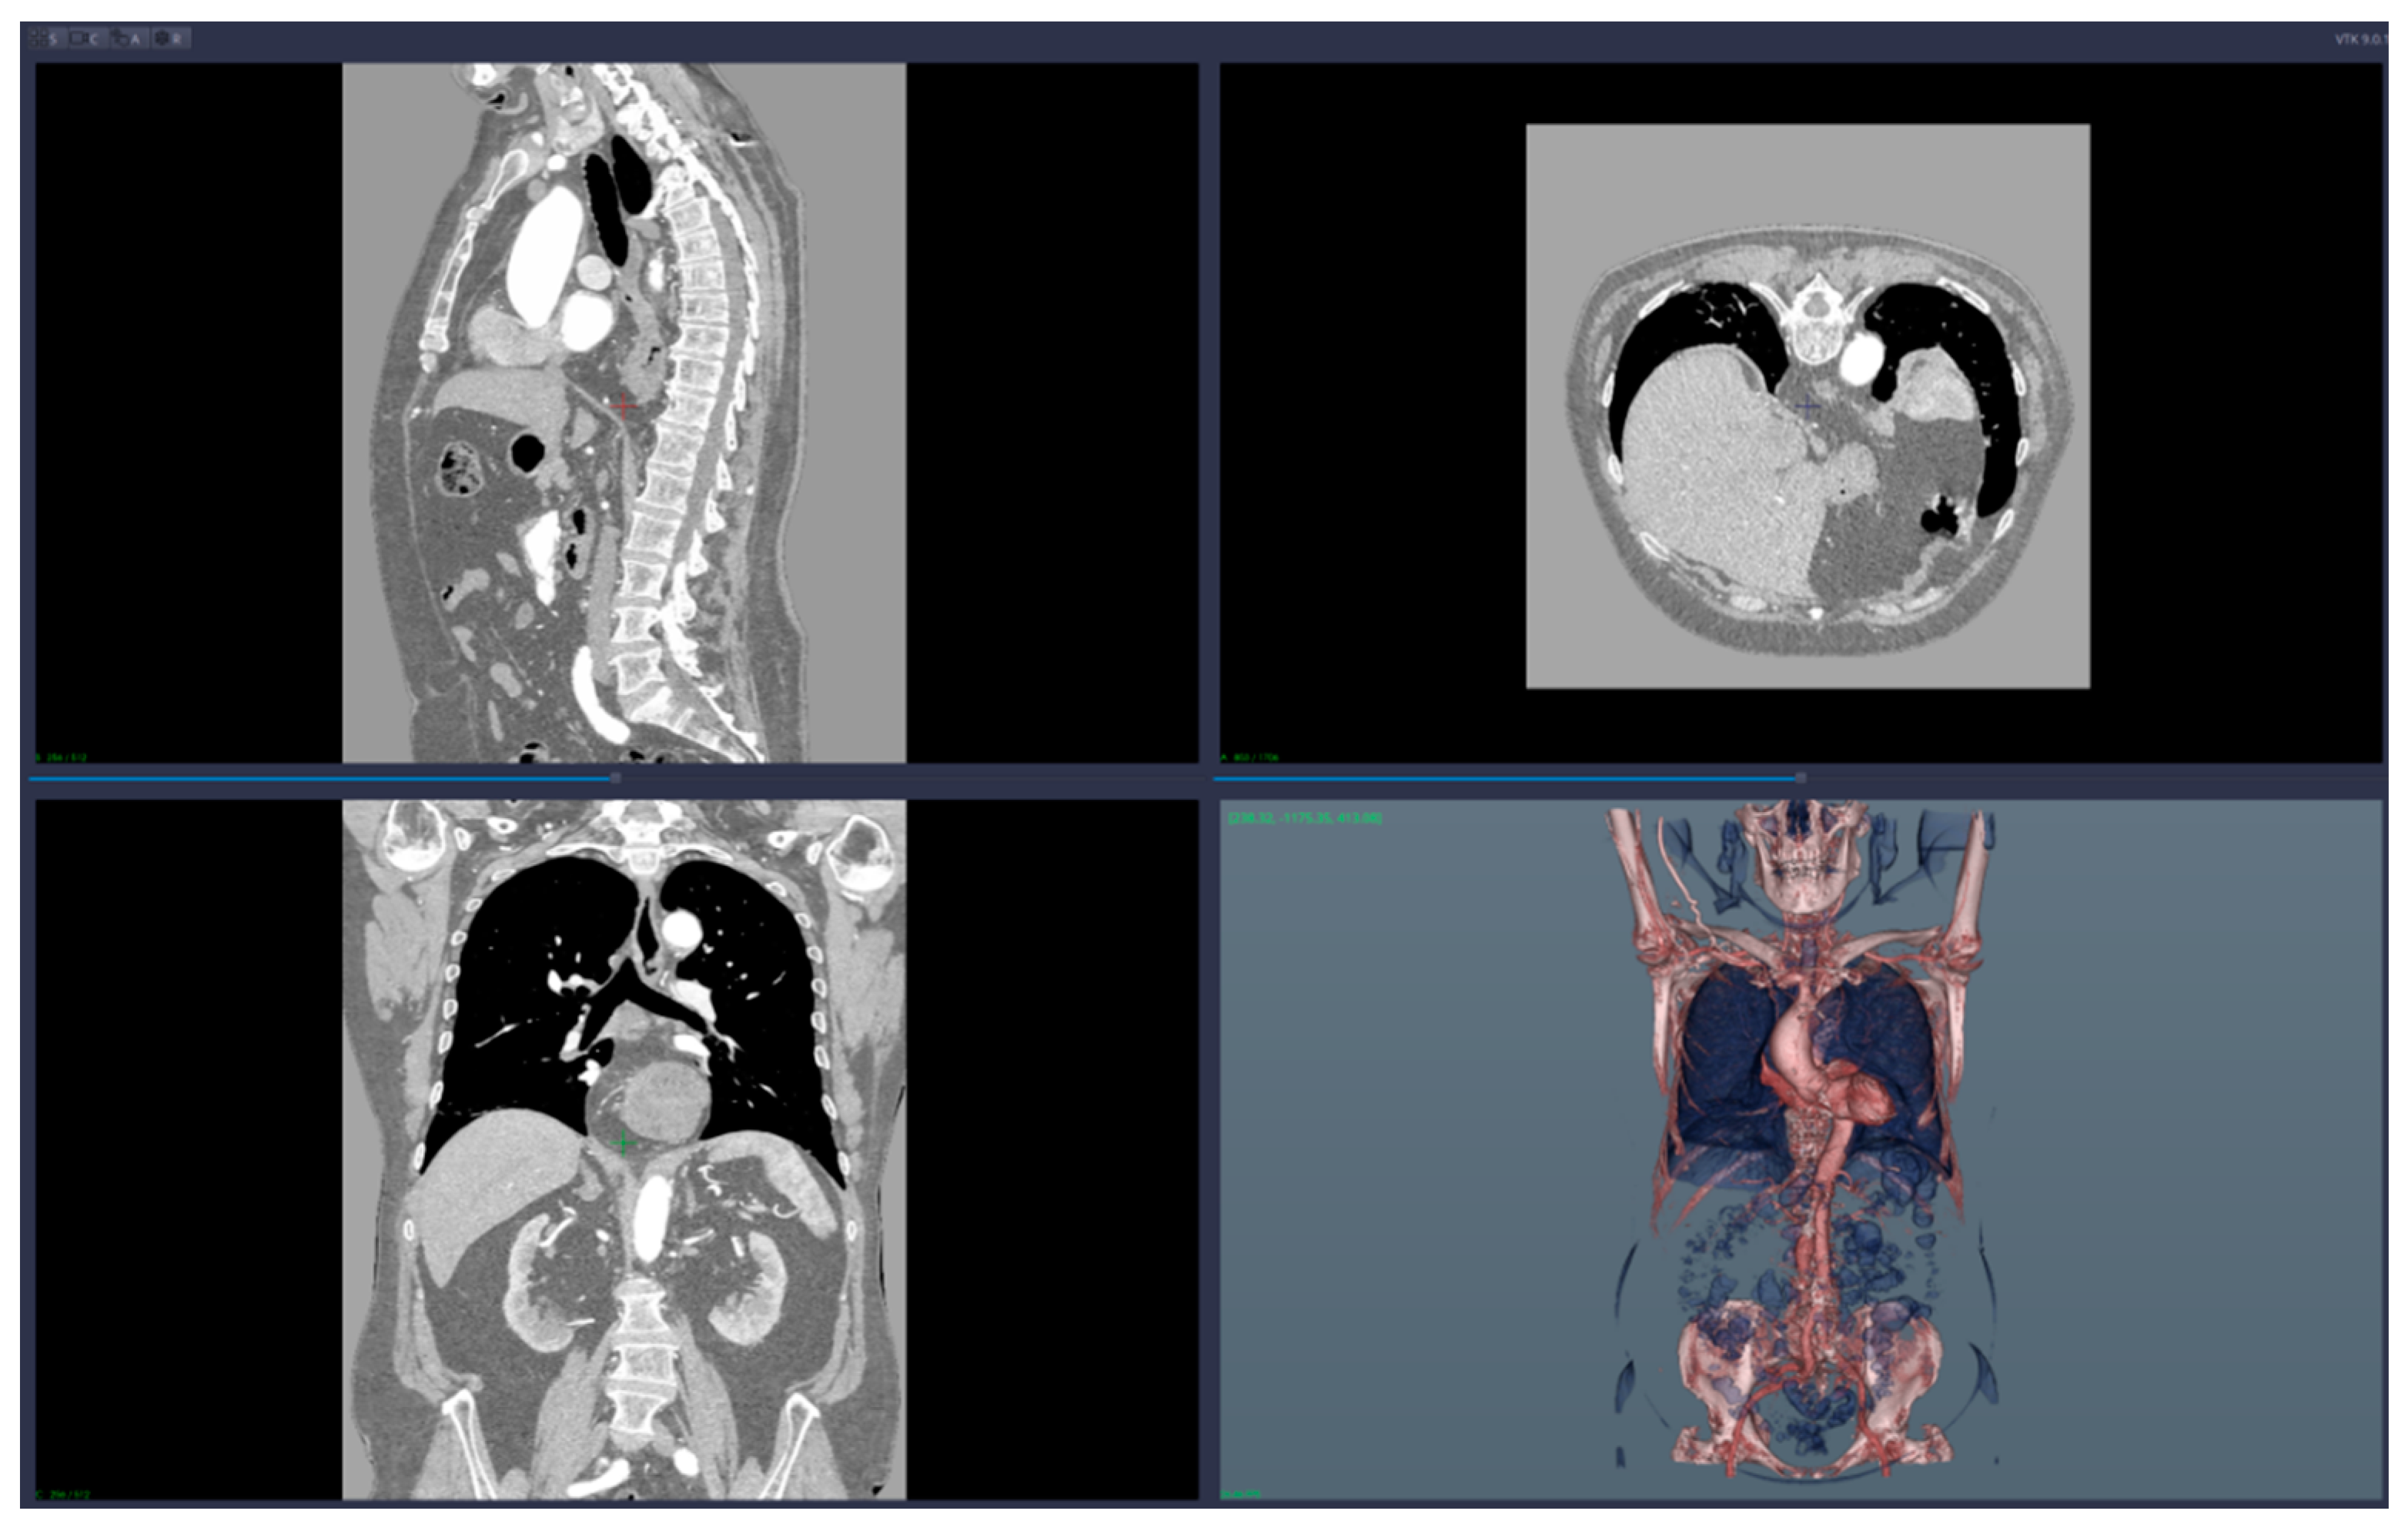

• 3D reconstruction and visualization of arteries (see Figure 1 and Figure 2)

• Virtual angiography—virtual 3D navigation through the mesenteric artery and aneurysm zone (see Figure 3, Figure 4, Figure 5, Figure 6 and Figure 7)

The 3D reconstruction and the visualization of arteries are based on the concept of a transfer function, which translates Hounsfield units from the CT data into colors and levels of opacity for the 3D-rendering scene. CardioCTNav implements a “freehand” drawing mode of the transfer function shapes; in this way, it allows fine-tuning in the selection of the tissues that are visualized (this fine-tuning is necessary for virtual navigation/angiography).

We applied the suggested pre-operatory planning procedure on CT data from a male patient aged 74. The scans were performed using a Siemens Somatom go. Top 128 slice machine [18], with contrast substance (ULTRAVIST 370 I.V.). The series used for planning took 647 slices at a distance of 0.99 mm each. The reconstructed 3D image had 655 × 512 × 647 voxels.

Figure 1. Images of the 3D CT reconstruction and 2D sections.

Figure 2. Images of the 3D reconstruction of main arteries and mesenteric artery aneurysm.